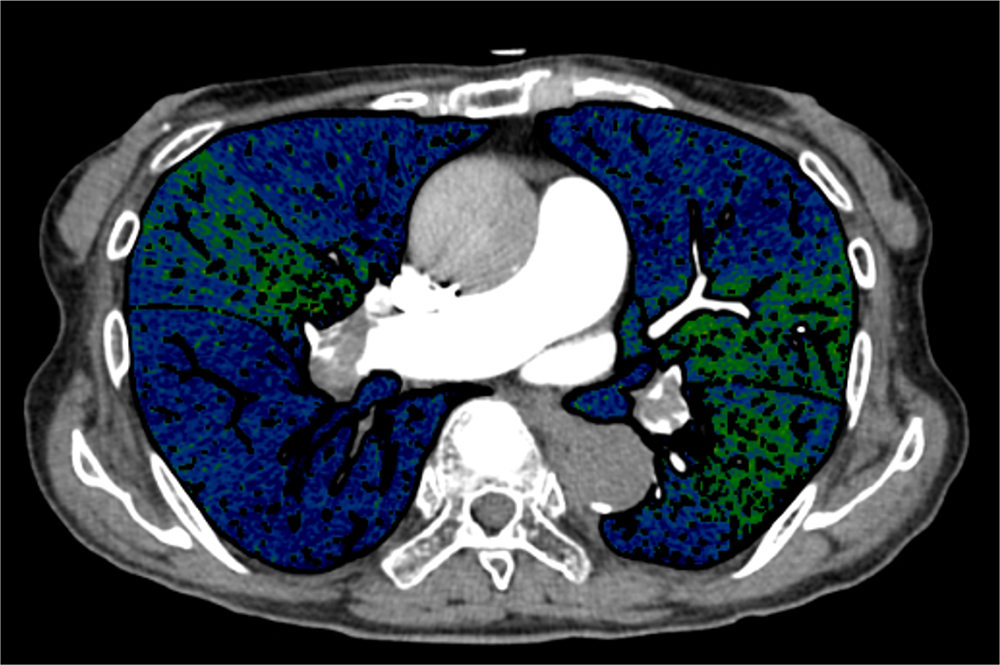

図2.図1と同部位のヨード密度画像

血流低下域(青色部分)が広範に認められる。